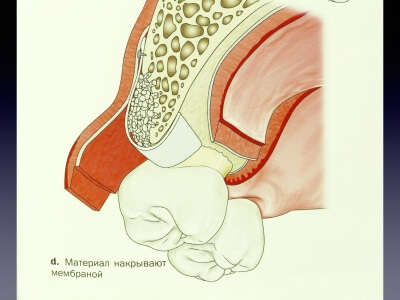

В данном кейсе автор при помощи Биоматрикса (мембрана) и Биоимплантат ГАП пошагово показывает, как спасти имплантат от развившегося периимплантита в следствии краевой резорбции.

Обратите внимание на обработку кости и самого имплантата от гранулята и произошедшей краевой резорбции.

Показан отдаленный результат (2 года) такого протокола лечения